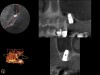

A 74-year-old male patient presented with about 4 mm to 5 mm of native bone in the No. 4 position (Figure 17). A composite graft, as described in Case 1, was used, as was the same implant type, but the implant was 11.5 mm in length with a taper of 5 mm to 4.2 mm. The approximately 16-month post-healed floor of the sinus was raised about 7 mm to 8 mm (Figure 18). The CBCT scan taken at 16 months postoperatively showed no change in appearance from the area of the old floor of the sinus to the new bone formed (Figure 19). Although it was endodontically involved, tooth No. 15 was not extracted, against professional advice. As can be seen in Figure 18, the No. 14 implant is acting as a bridge abutment.

This patient was a 73-year-old man with only about 3.5 mm of native bone in the No. 3 site (Figure 20). The composite graft used here was a 50:50 mixture of DFDBA and deproteinized bovine bone mineral (Osteohealth, www.osteohealth.com) with approximately 40% calcium sulfate added. The implant was the same type and length as in Case 1 above. Figure 21 shows the area on the day of placement. In the CBCT scan on the day of placement (Figure 22), the native bone and bone graft were clearly discernable. However, the postoperative radiograph taken at 6.5 months (Figure 23) showed no marginal bone loss and a significantly denser appearance than when the graft was place. The membrane was raised about 7 mm to 8 mm. The final radiograph was taken after extraction of tooth No. 2 and after extraction of tooth No. 4 and immediate implant placement.